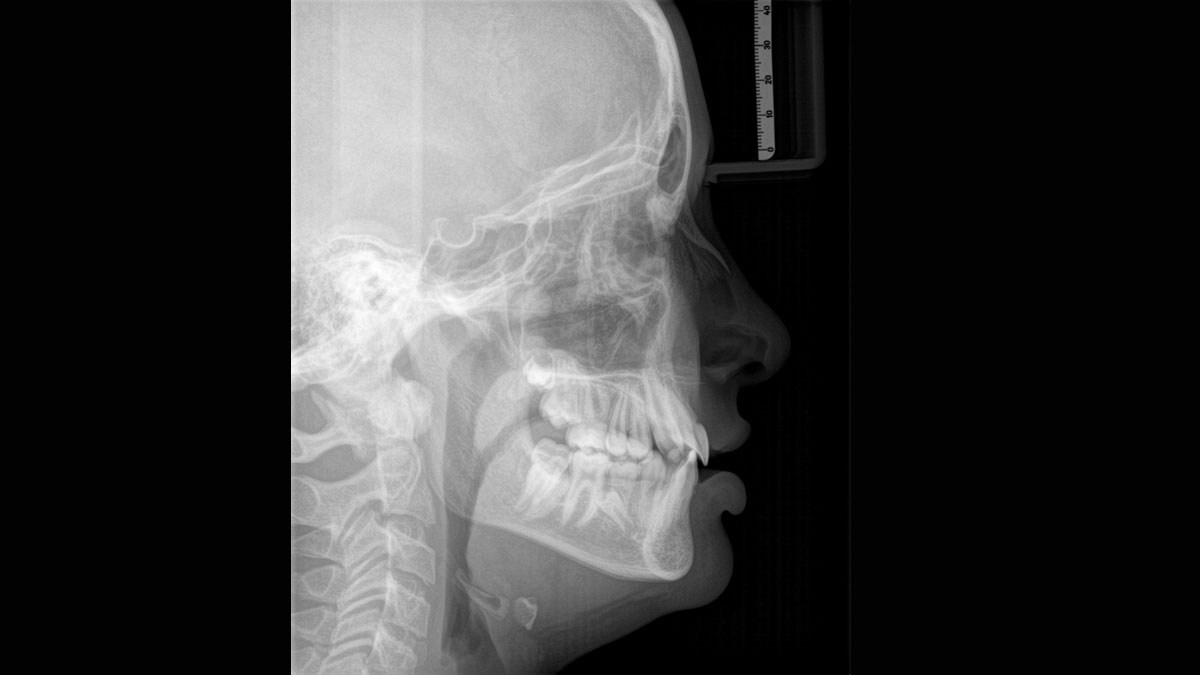

Für außergewöhnliche Panoramabilder mit hoher Schärfe. Sie können einen optionalen rechten oder linken Fernröntgenausleger wählen, der jederzeit nachgerüstet werden kann.

Dank des optimierten Low Dose Modus mit dediziertem Filter wird die Abbildung dichter Strukturen wie etwa Knochen bei stark reduzierter Dosis ermöglicht. Das macht Intelligent Low Dose zu einer attraktiven und effizienten Option bei vielen klinischen Fällen. Ob in der Kieferorthopädie oder Implantologie – mit den Dentsply Sirona Lösungen finden Sie für jeden Fall die optimale Einstellung.